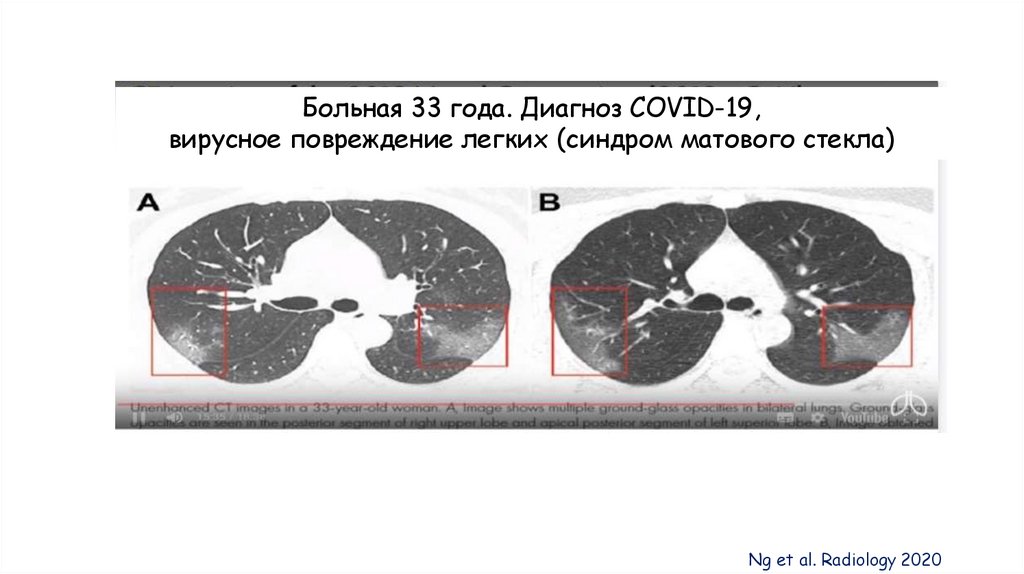

Больная 33 года. Диагноз COVID-19,

вирусное повреждение легких (синдром матового стекла)

Ng et al. Radiology 2020

ВРКТ – наиболее чувствительный метод для диагностики

поражения легких при COVID-19!